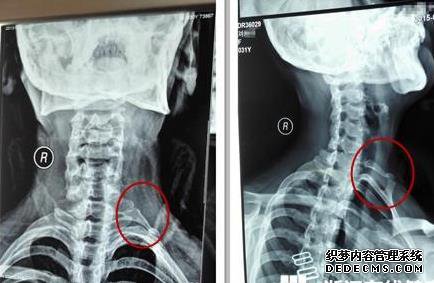

在这种情况下,一般考虑的是软骨软骨的成本。

长期姿势,主要是在电脑手机前工作,长时间在桌子上工作,睡觉,挤压骨头,软组织发炎并形成轻微疼痛。

如果改变这些不良生活方式并对症治疗,就无法缓解。我们还将考虑是否存在内脏病变,例如胃炎,肝胆和胰腺疾病,这些疾病会引起两侧肋骨下的轻度疼痛,但通常被认为是深沉的钝痛。

肋骨的非化脓性病变(例如肺结核和肿瘤)可引起轻度疼痛,而这些疾病在早期疼痛中不太明显。